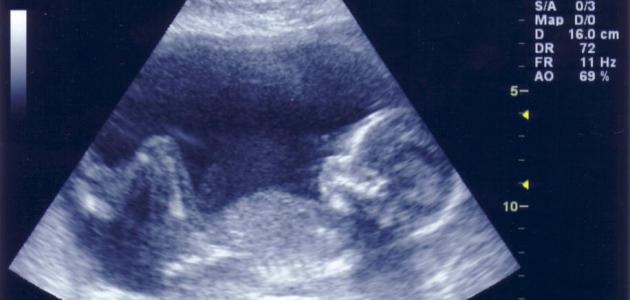

صورة جنين

اكتشف فريق من الباحثين الفرنسيين فى الأكاديمية العلمية الفرنسية، بفضل استخدامهم لأشعة الإيكو ثلاثية الأبعاد أن الأجنة في بطون أمهاتهم تتثاءب وذلك وفقا لعمر كل جنين.

كما تبين من الدراسة التي أجراها الفريق أن عملية التثاؤب تعمل على تنشيط مادة الأوكسيتوسين في منطقة المهاد في المخ التي تؤثر على المستقبلات العضلية في الخلايا، خاصة عضلات الحنجرة والوجه والفك لضمان عملية التثاؤب بشكل آمن بين الأجنة في رحم الأم .